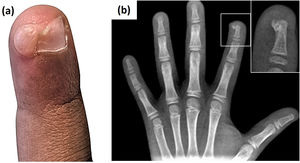

A 8-year-old boy presented with a 4-month history of a 1-cm erythematous, friable nodule on the distal phalanx of the left second finger. There was no history of trauma. Based on the clinical characteristics of the lesion, the diagnosis of pyogenic granuloma was assumed, and curettage of the lesion was performed. The histopathological examination was nonspecific. Two weeks later, a 1-cm flesh-colored nodule with nail elevation and onycholysis appeared in that location (Fig. 1a). The diagnosis of subungual exostosis was confirmed by radiography, revealing a calcifying projection on the dorsal part of the distal phalanx (Fig. 1b). Surgical resection of the lesion was performed.